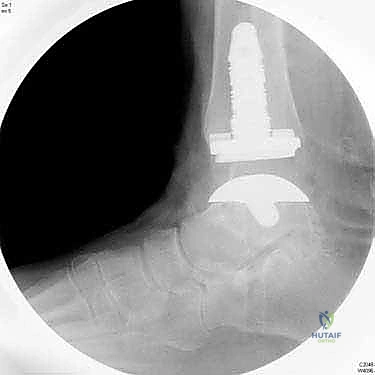

5. تركيب المكونات المفصلية

يتم تثبيت القاعدة المعدنية السفلية على عظمة القعب (Talus). ثم يتم إدخال قطعة بلاستيكية عالية التحمل (بولي إيثيلين) بين القطعتين المعدنيتين. هذه القطعة البلاستيكية تعمل كغضروف صناعي، مما يسمح للمفصل بالانزلاق بحرية وسلاسة تامة.

6. التحقق والإغلاق

يتم فحص المدى الحركي للكاحل الجديد وثباته تحت جهاز الأشعة السينية (Fluoroscopy) داخل غرفة العمليات للتأكد من المحاذاة المثالية بنسبة 100%. بعد ذلك، يتم إغلاق الشق الجراحي بغرز تجميلية، ووضع جبيرة ناعمة أو حذاء طبي واقٍ.